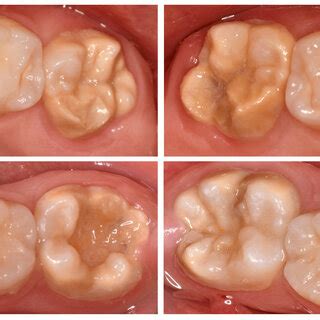

A pesar de los esfuerzos de cepillado y uso de hilo dental, los dientes posteriores de los niños son propensos a las caries debido a sus surcos profundos. Estos dientes, con sus surcos y fisuras naturales, son áreas propensas a la acumulación de placa bacteriana y restos de alimentos. El sellado dental complementa esta rutina al ofrecer una capa adicional de protección. Por lo tanto, el sellado dental para niños no solo es una medida preventiva, sino también una inversión en su salud bucal a largo plazo.

Un sellador oclusal o dental es un material compuesto por resina que se aplica sobre la superficie masticatoria de los premolares y molares en niños y adolescentes. Utilizado desde hace décadas, el sellado dental consiste -como su nombre indica- en sellar las fosas y fisuras de los dientes que pueden favorecer el crecimiento de bacterias y gérmenes, que, a su vez, transforman los restos de comida y azúcares en ácidos que dañarán el esmalte y provocarán la caries.

Los selladores dentales modernos generalmente están hechos a base de resina o de ionómero de vidrio. Esta zona resulta especialmente irregular y rugosa, por lo que se convierte en el lugar idóneo para que las bacterias se acumulen. Son estos agentes patógenos los que liberan ácidos que terminan desarrollando las caries.

De hecho, se ha demostrado que los selladores reducen el riesgo de caries en casi un 80% en los molares. Los selladores actúan como impermeables para los dientes. Cuando las bacterias que viven en la boca y causan caries se encuentran con las partículas de comida sobrantes, producen ácidos que pueden crear agujeros y cavidades en los dientes.

La aplicación de selladores en fosas y fisuras dentales es una técnica altamente eficaz y que contribuye a cuidar la salud oral de los más pequeños. Así lo confirman entidades como la Sociedad Española de Odontopediatría, que define las lesiones cariosas de las fisuras dentales como las más frecuentes. De hecho, representan entre el 80 y el 90% de la totalidad de caries que afectan a las muelas en general, y el 44% de los dientes de leche.